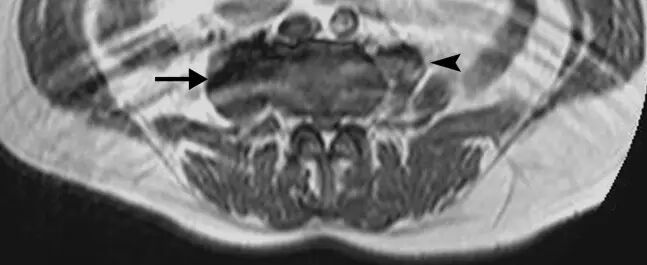

![]()

图24.骨骼肌损伤和肌坏死。 该患者,在坠落后发生的右大腿中的受污染伤口导致感染性肌坏死。 (a)轴向T2加权MRI图像显示肿大的内收肌和股二头肌----(肌肉)由于水肿扩散高信号强度。 在大收肌(箭头)中看到中心区域与流体聚集相一致。 (b)冠状动脉脂肪抑制T2加权磁共振成像显示弥漫性水肿在大腿近端的后房(箭头)。 其信号空隙肌内气体被看作指示严重感染(气性坏疽)的存在(箭头)。 感染区域的培养物显示破伤风杆菌。